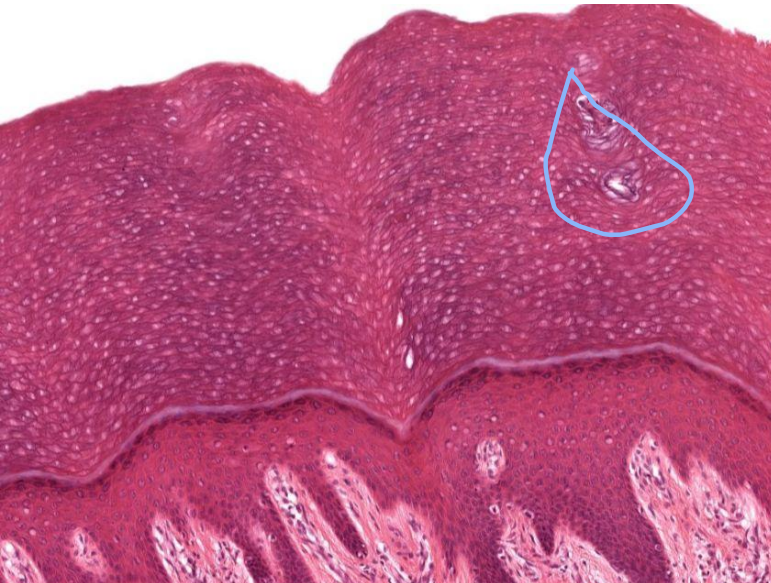

What is the Stratum Corneum?

Dead cells

Flattened scales

Densely packed keratin

What is the Stratum Lucidum?

A layer in thick skin

Soles of feet and palms of hands

Glabrous skin → devoid of hair

What is circled here?

Sweat glands

What is layer is circled here?

Stratum Lucidum

What does Stratum Lucidum do?

Act as a water barrier

Made up of anucleated keratinocytes

Name the layers top to bottom?

Dermis, epidermis, Stratum Lucidum, Corneum